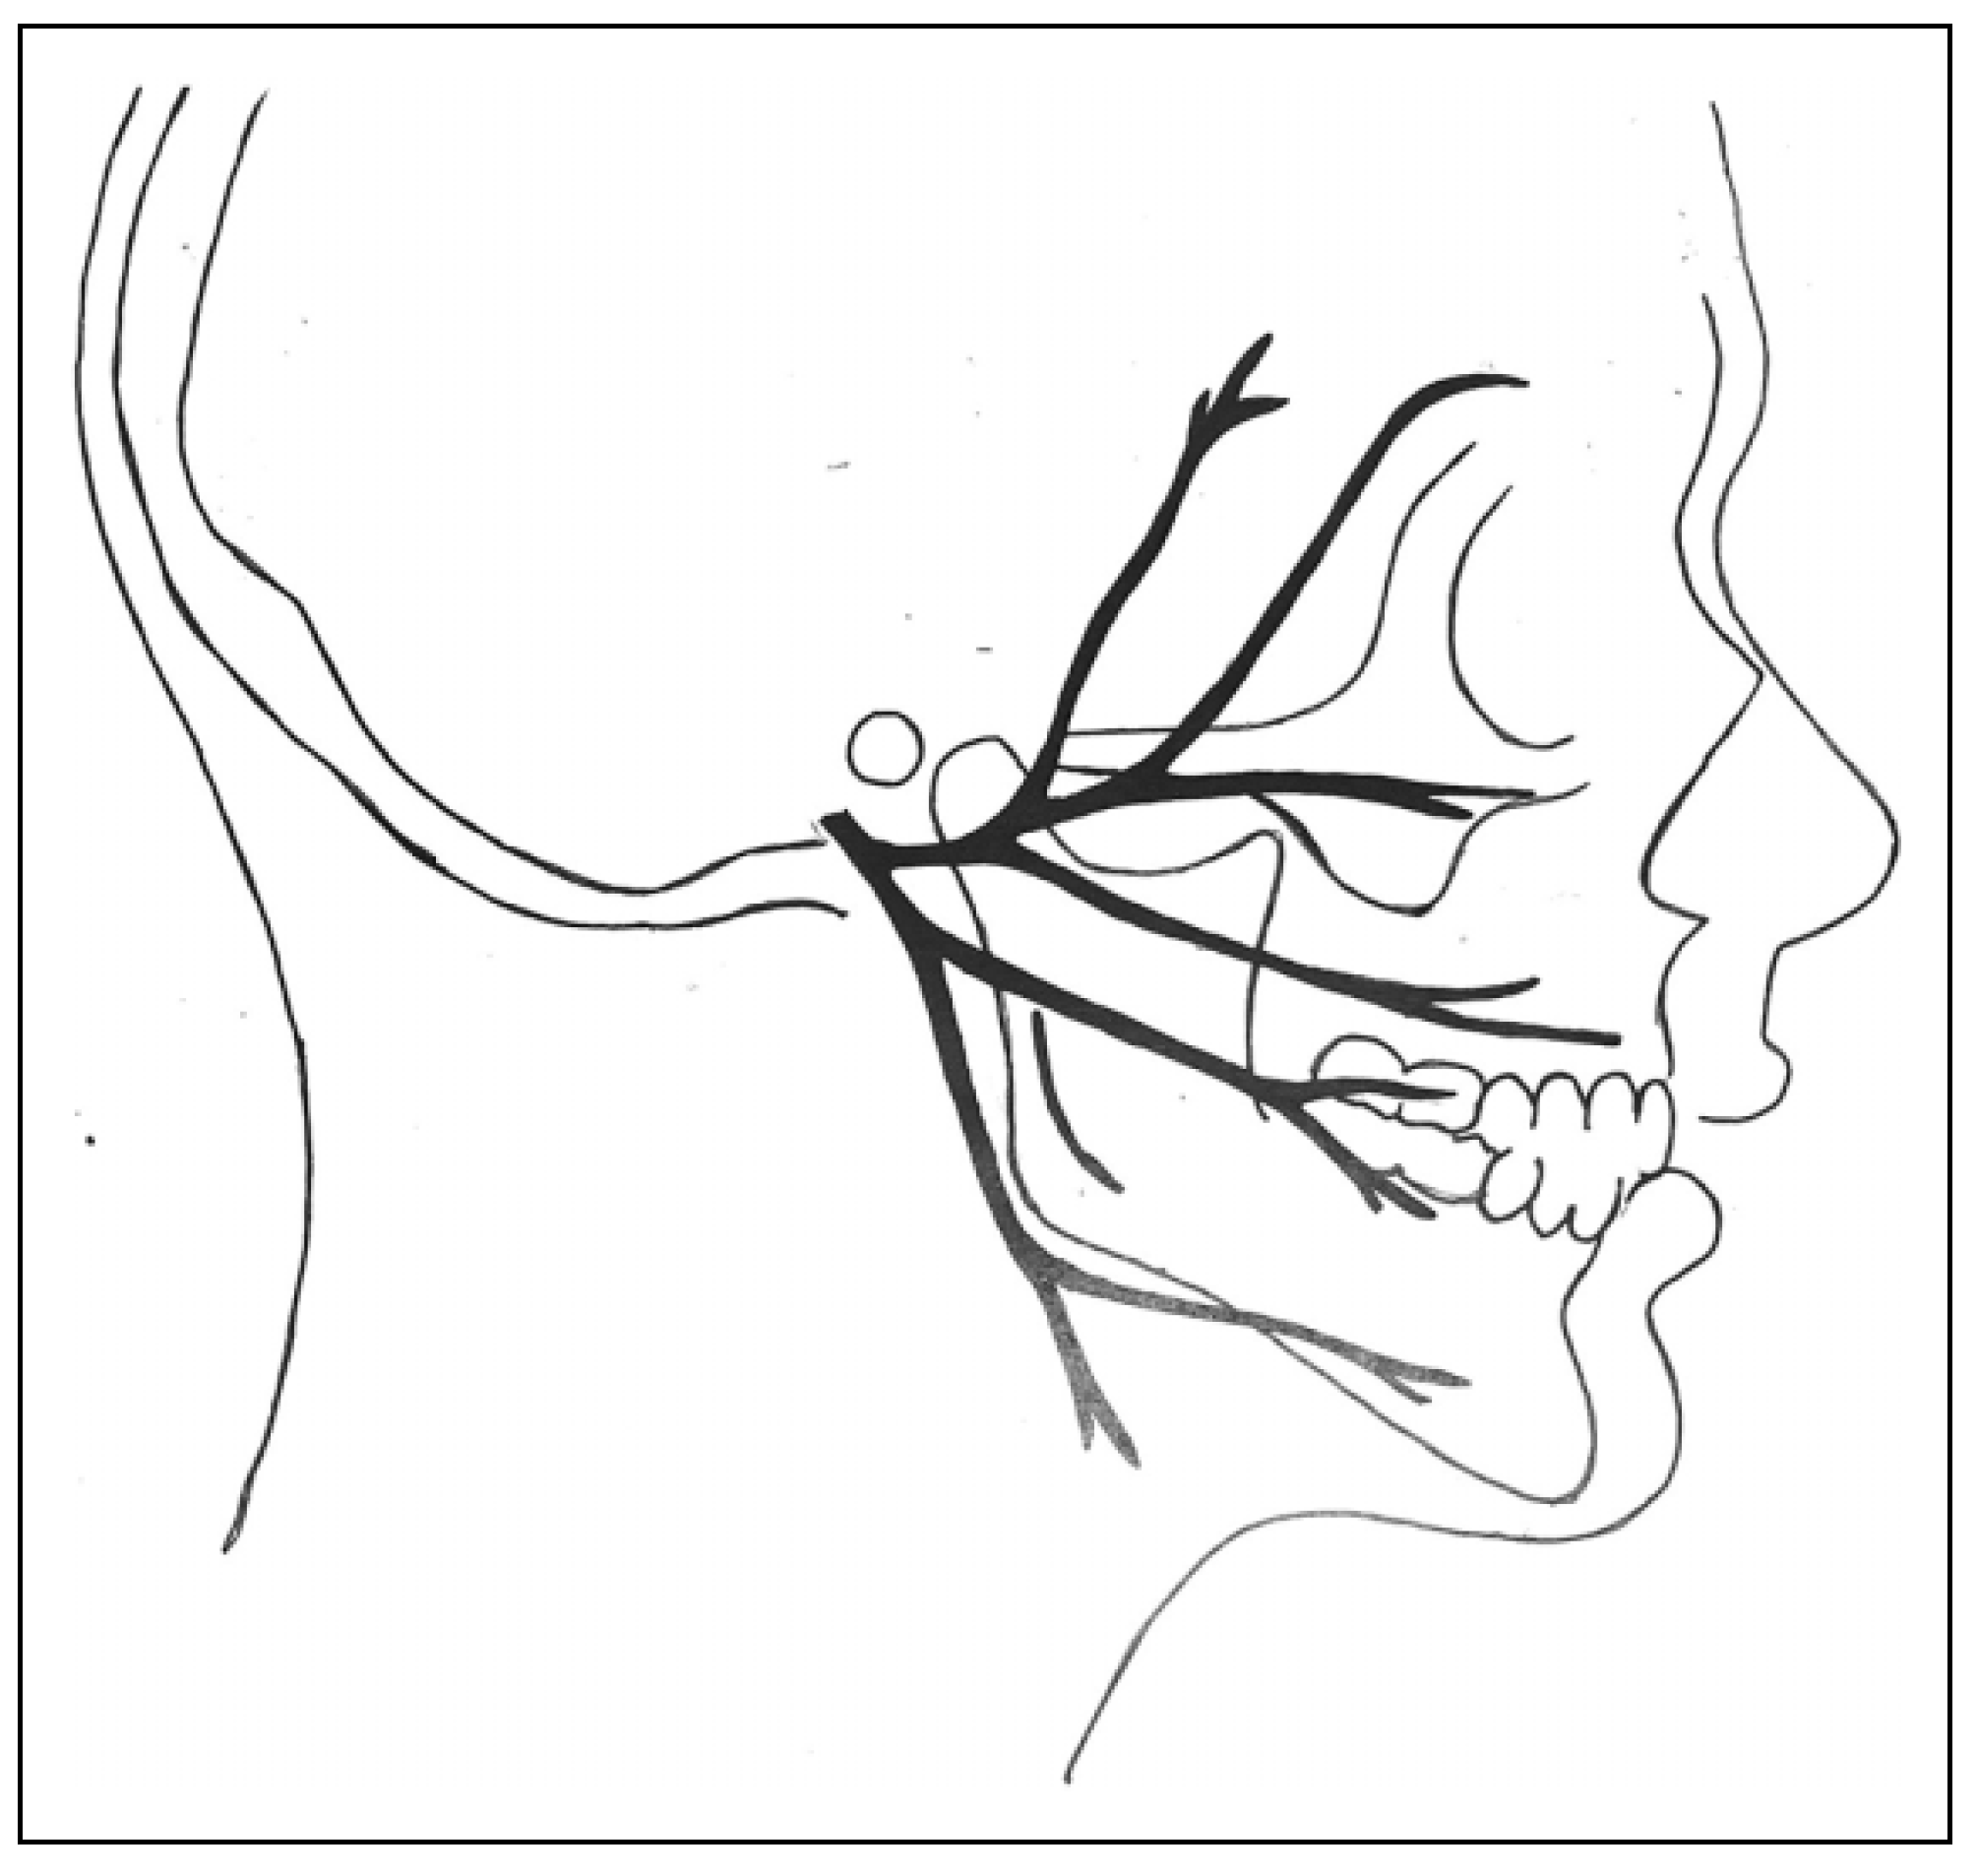

Surgical Procedure

- Imai T, Fujita Y, Motoki A, et al. Surgical approaches for condylar fractures related to facial nerve injury: deep versus superficial dissection. Int J Oral Maxillofac Surg, 1: 48(9), 1227. [CrossRef]